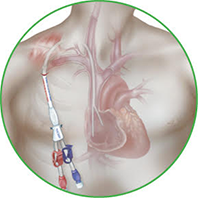

Cirurgia endovascular

- Tratamento com cateteres e guias

- Implante de stents e endopróteses

- Menor trauma cirúrgico